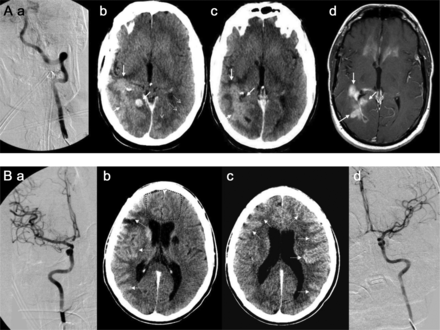

43岁的男人(A)与多形性胶质母细胞瘤(GBM)接受了血脑屏障的破坏(BBBD)通过左椎动脉导管造影(A)。在30分钟,对比增强CT表现,说明增强两国后大脑皮层的动脉(PCA)分布(虚线箭头表示正常皮质增强左侧)与增强肿瘤边缘围绕正确的侧脑室后角的(箭头,b, c),指出在postcontrast t1加权磁共振成像(d)。一个34岁的男人(b)与“绿带运动”接受了右颈内动脉(ICA)导管BBBD (A),与合成右大脑中动脉(MCA)分布增强(虚线箭头,b),备件ACA分布(虚线轮廓,c);缺乏cross-filling注意到A1段ACA,以及正确的MCA,通过前动脉和缺乏沟通PCA皮质分布增强(a)。第二天,病人接受导管BBBD通过ICA左边,与示范的双边ACA皮质分布增强(虚线箭头,c),这可能是由于为两国留住好的cross-filling以及A1段正确的ACA、MCA,看到通过ICA (d)。

立即后动脉内的溶栓头CT (A)展示了一个新领域内的hyperdensity离开豆状核(A)。十四个小时postprocedure头部CT显示持久hyperdensity,损失的灰白色分化在左parieto-temporal凸性,并抹杀左侧侧脑室CT扫描主管(b)。随访36小时,60个小时持续hyperdensity左壳,建议外渗与脑水肿和中线移位(c, d)。头部CT动脉内的溶栓后立即(b)显示了一个hyperdensity正确的硬膜(A),解决完全重复头上CT表现16小时postprocedure (b),显示对比度增强。

几个机制假设对比造影剂外渗和出血有关。19最有说服力的毒性在基板,包括对比BBB的结构性障碍与干扰。它导致溢出的血液细胞元素从微血管,反过来,导致对比外渗(定义为hyperdensity暗示对比[Hounsfield单位> 90])在24小时(图4A)。相比之下,对比度增强是由于从血管造影剂泄漏到细胞外空间,由于BBB的渗透性增加。头部CT二次的hyperdensity对比度增强通常在24小时内清理(图4B)。对比溢出已被证明有一个强大的协会与HT以及预后不良。20.